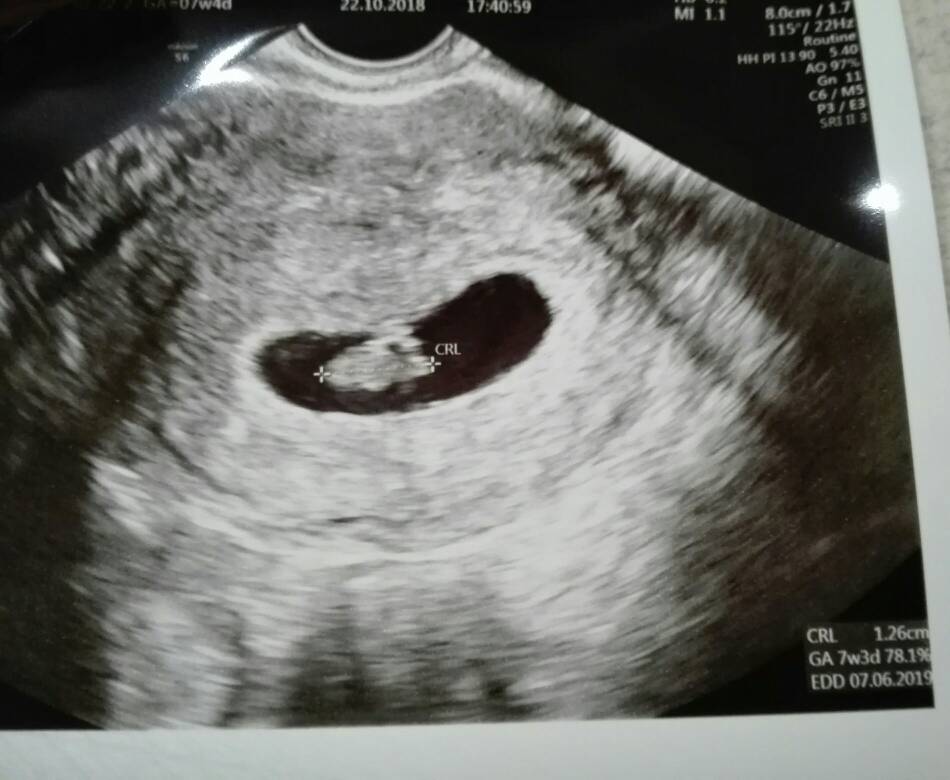

Powiem ci ze nie ogarniam tego [emoji23] tak to u mnie wyglada i nie mam pojecia [emoji23]

IMG_20181022_181940.jpg

• IMG_20181030_184414.jpg

IMG_20181030_184414.jpg

67,8 KB · Wyświetleń: 339